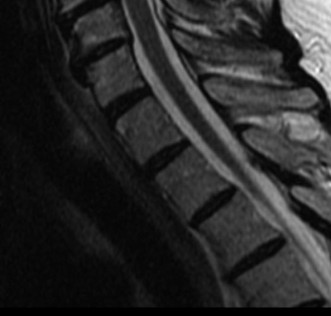

CASE 1 A 63-year-old male sustained a hyperextension injury to his neck while diving into a pool. Upon presentation, he reports decreased sensation in his hands and decreased strength in his arms and wrists, but no lower extremity complaints. On motor examination, he has 5/5 strength in his deltoids and elbow flexors and 4/5 strength in the elbow extensors, wrist extensors, and finger flexors. Lower extremity motor examination is normal. Sensation is decreased to light touch in both hands. Otherwise his sensation is preserved. Images of his cervical spine are shown in Figures 1–1 to 1–3.

Figure 1–3

The correct answer is (B). The clinical scenario describes a patient with central cord syndrome (CCS). CCS continues to be the most common incomplete spinal cord injury accounting for 15.7% to 25% of all spinal cord injuries. The characteristic presentation is an extension moment injury in a previously spondylotic and stenotic spine. Figures 1–1 to 1–3 demonstrate a spondylotic spine with central narrowing and CSF effacement that is worst at the C3–4 level. Bleeding, edema, and/or Wallerian degeneration lead to damage of the lateral corticospinal tract which is the main descending motor tract in the spinal cord. The more central anatomic position of the homunculus to the upper extremities places them at greater risk than those to the lower extremities. As such, injury to the lateral corticospinal tract is characterized by upper more than lower extremity involvement and motor deficits being more pronounced than sensory deficits.